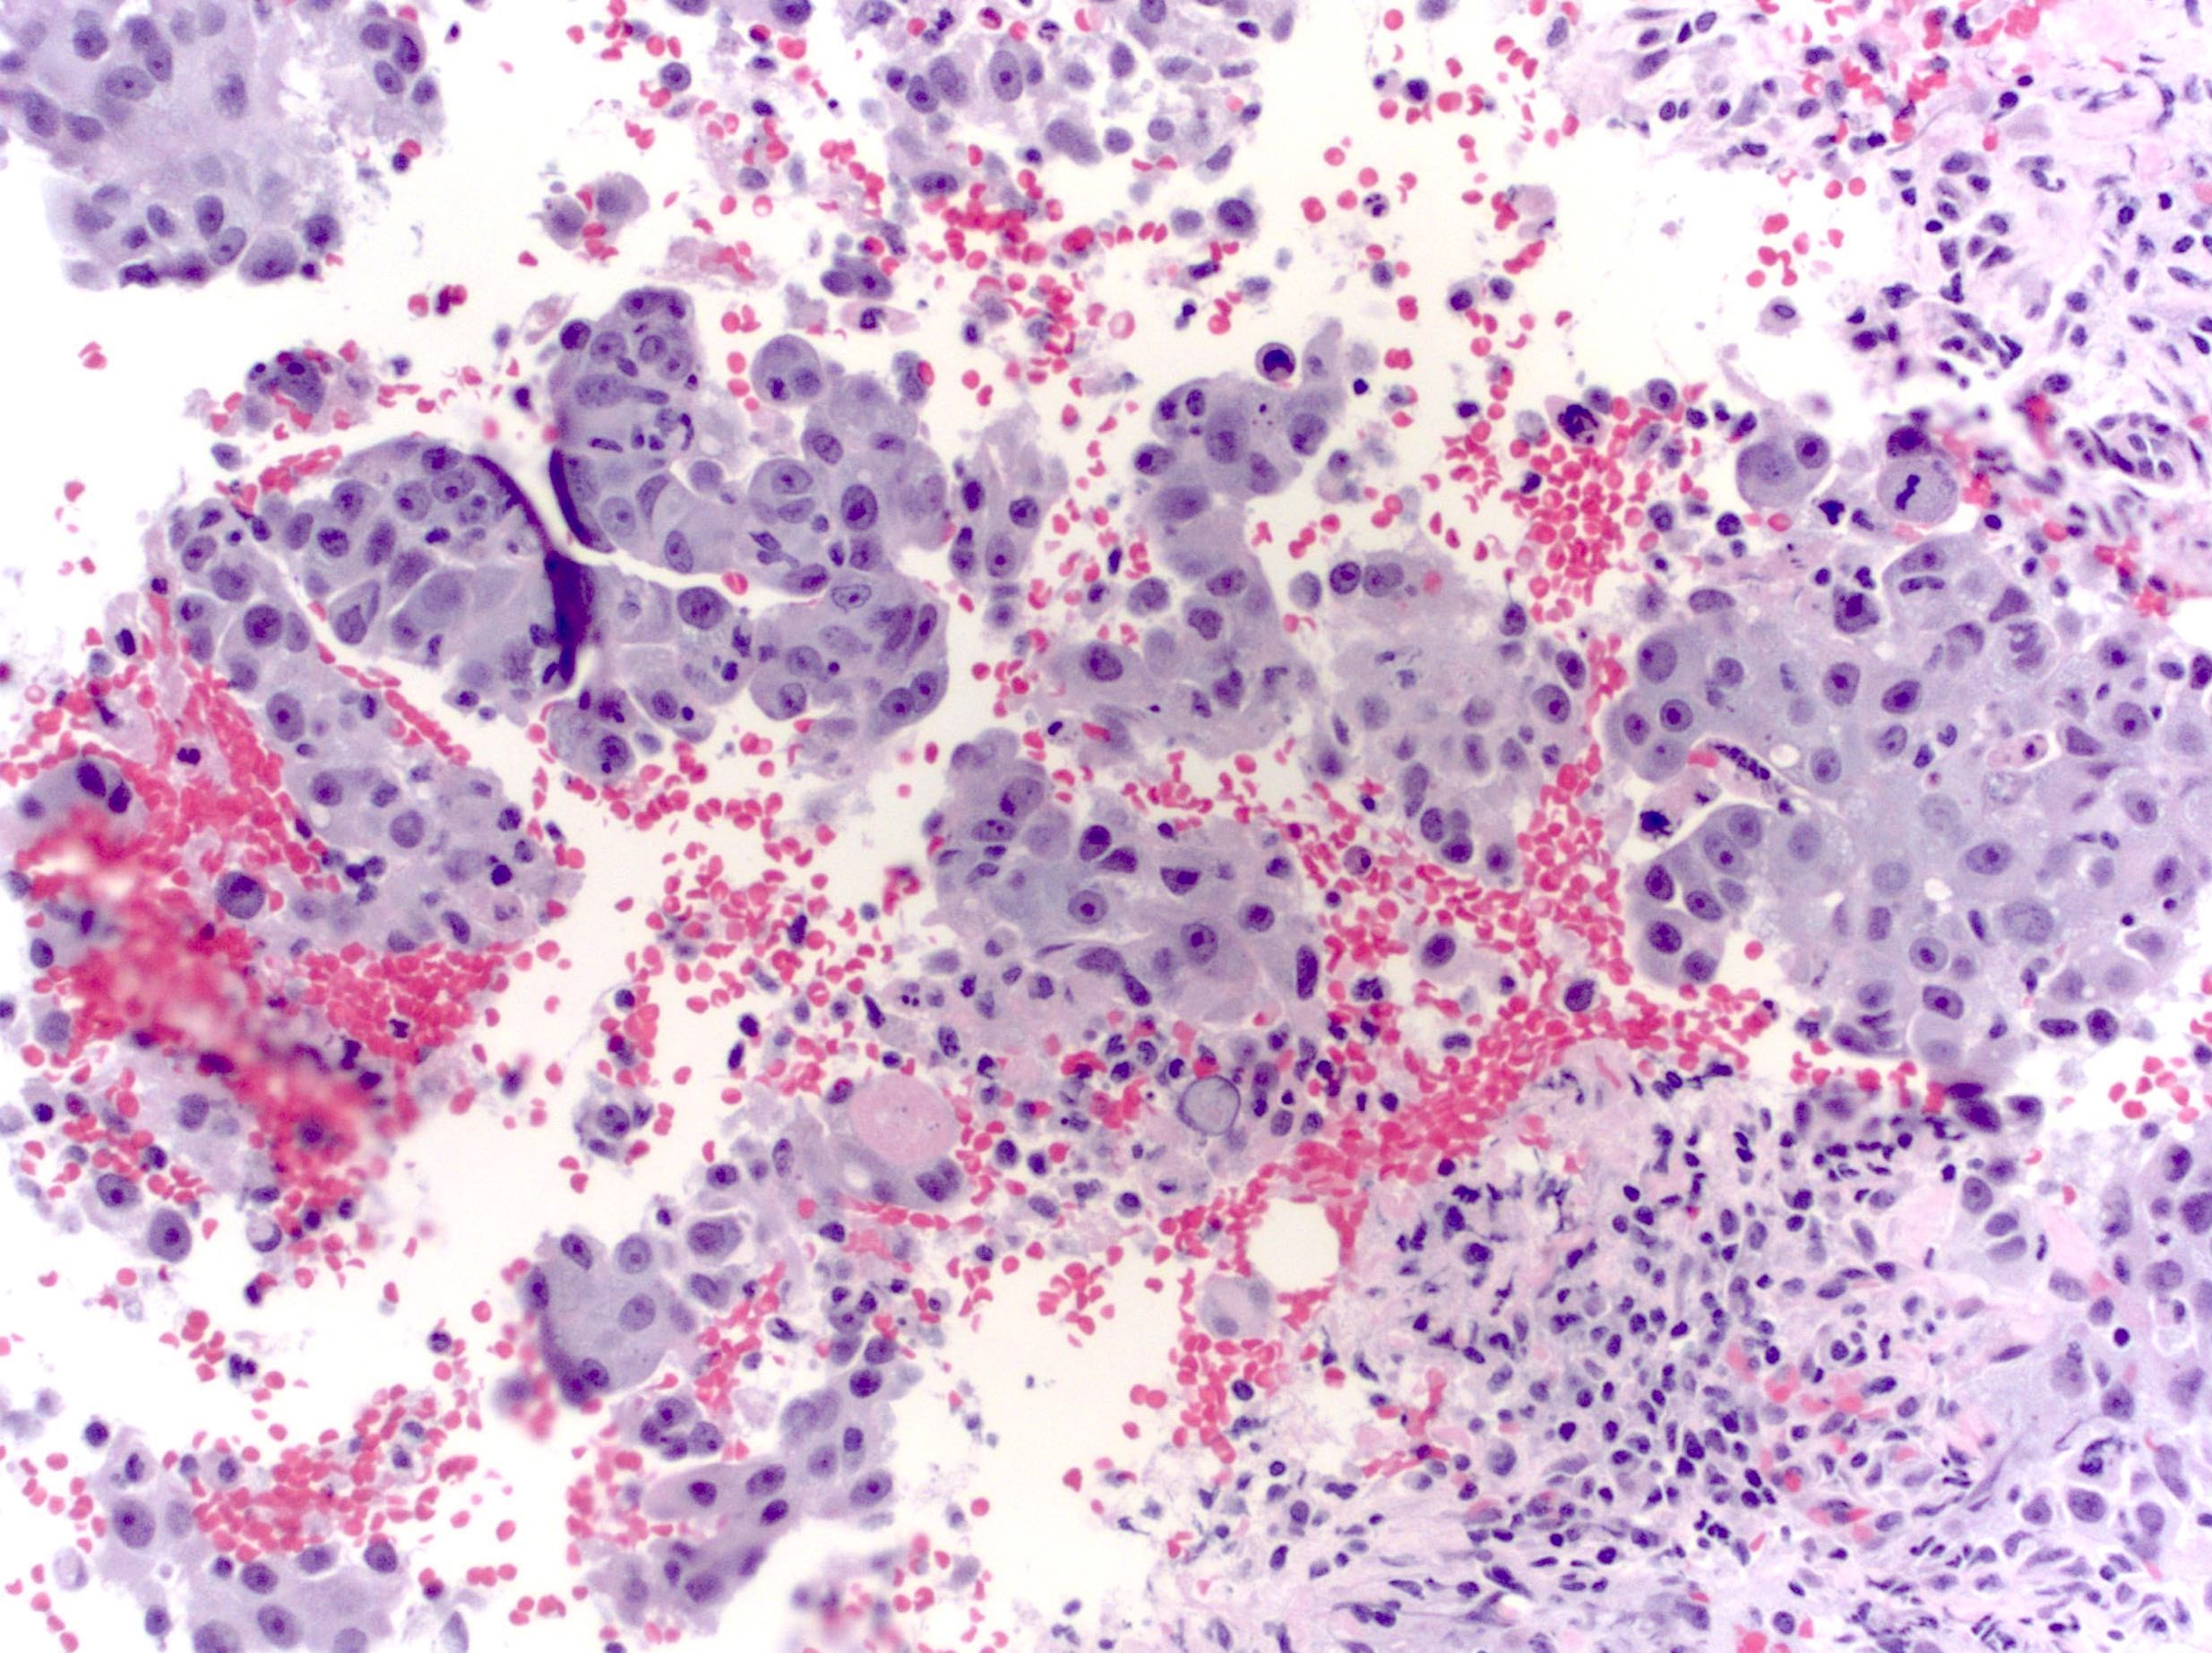

Microscopic (histologic) images

Contributed by Emily S. Reisenbichler, M.D., Andrey Bychkov, M.D., Ph.D., Maria Tretiakova, M.D., Ph.D. and Debra Zynger, M.D.

Positive staining - tumors

- Choriocarcinomas and gestational trophoblastic tumors (100%) (Hum Pathol 2016;48:18, Histopathology 2015;67:636)

- Neuroblastoma (100%) (Cancer Cytopathol 2017;125:940)